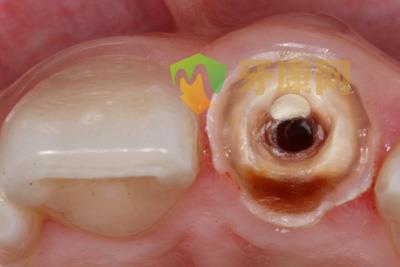

穿孔位置